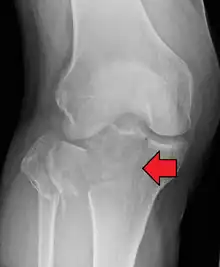

A tibial plateau fracture seen on X-ray